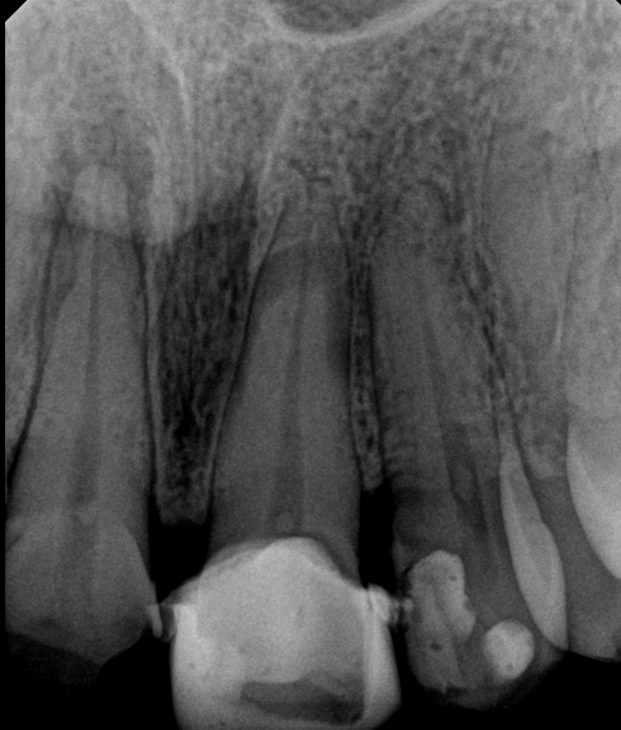

Case: RCT on Tooth #9

13-year-old male, healthy, no medications, no known allergies.

Dx: Necrotic pulp and acute apical abscess (#9).

Tx: Root canal therapy initiated.

Reflection

This case involved a necrotic tooth with an open apex and blunderbuss canal. Achieving apical control was a challenge due to the lack of a natural stop. Apexification was considered, but we managed to adapt a large master cone (#60), trimming the tip to get a snug fit and achieve proper tug-back, allowing us to complete obturation successfully.